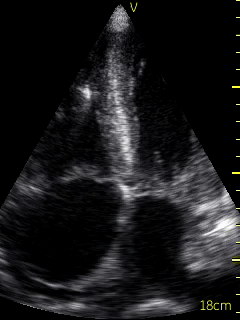

A bedside echocardiogram (VScan, GE) showed evidence of severe left ventricular and right ventricular thickening. Both atria were severely dilated. The mitral, tricuspid, and aortic valves appeared thickened. Myocardial speckling was not appreciated. Both the left and right ventricular function appeared to be moderately impaired.